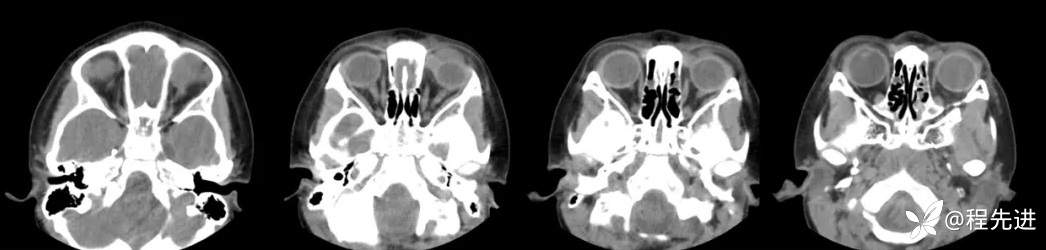

CT平扫: